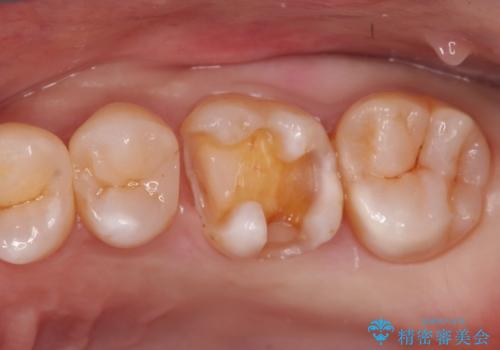

- 矯正終了後にメタルフリーの治療を希望された患者様です。

セラミックインレーにて修復治療を行なっております。

セラミックインレーのセット時にはラバーダムを用い防湿に気をつけて処置をしております。